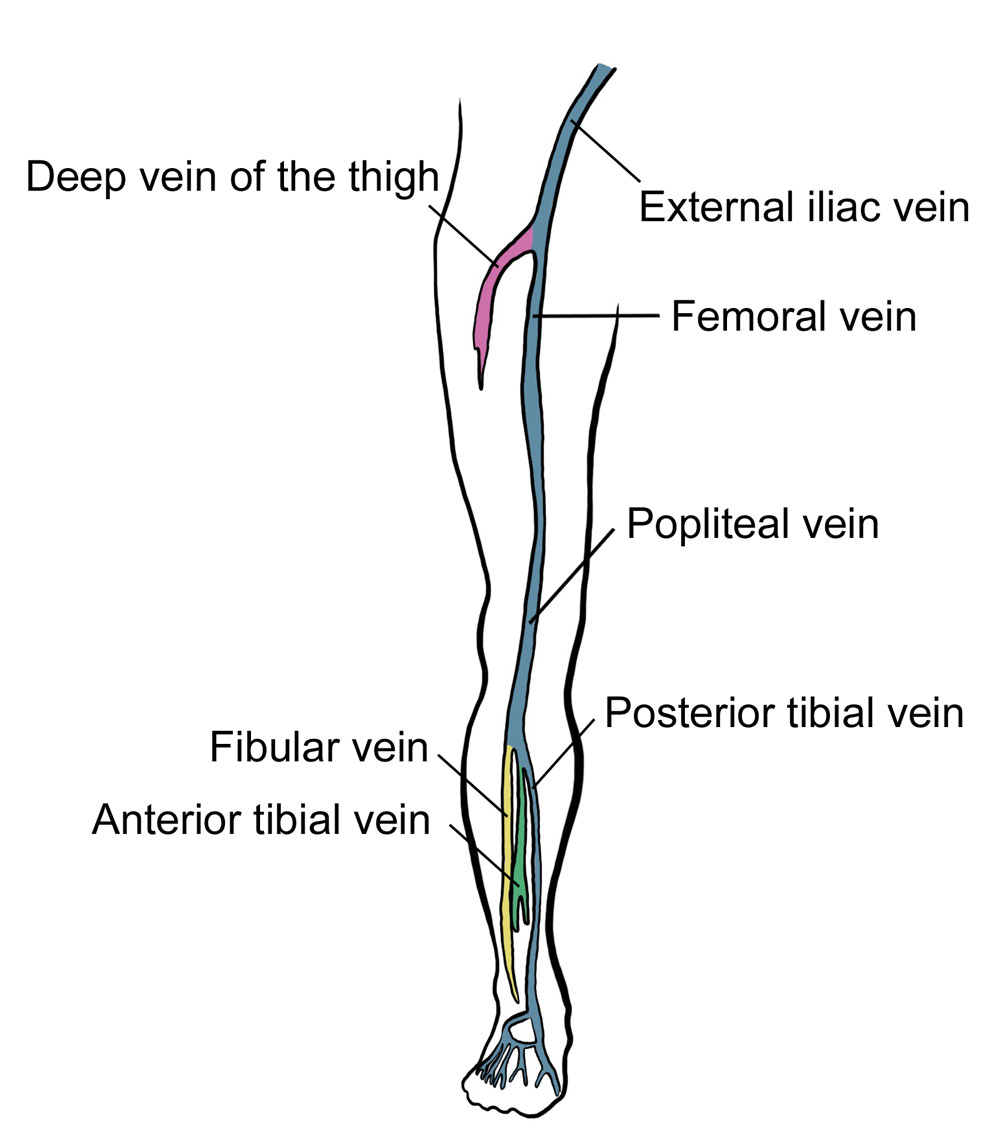

venous dvt deep thrombosis lower extremity system evlt

deep vein veins thrombosis leg

extremity venous thrombosis